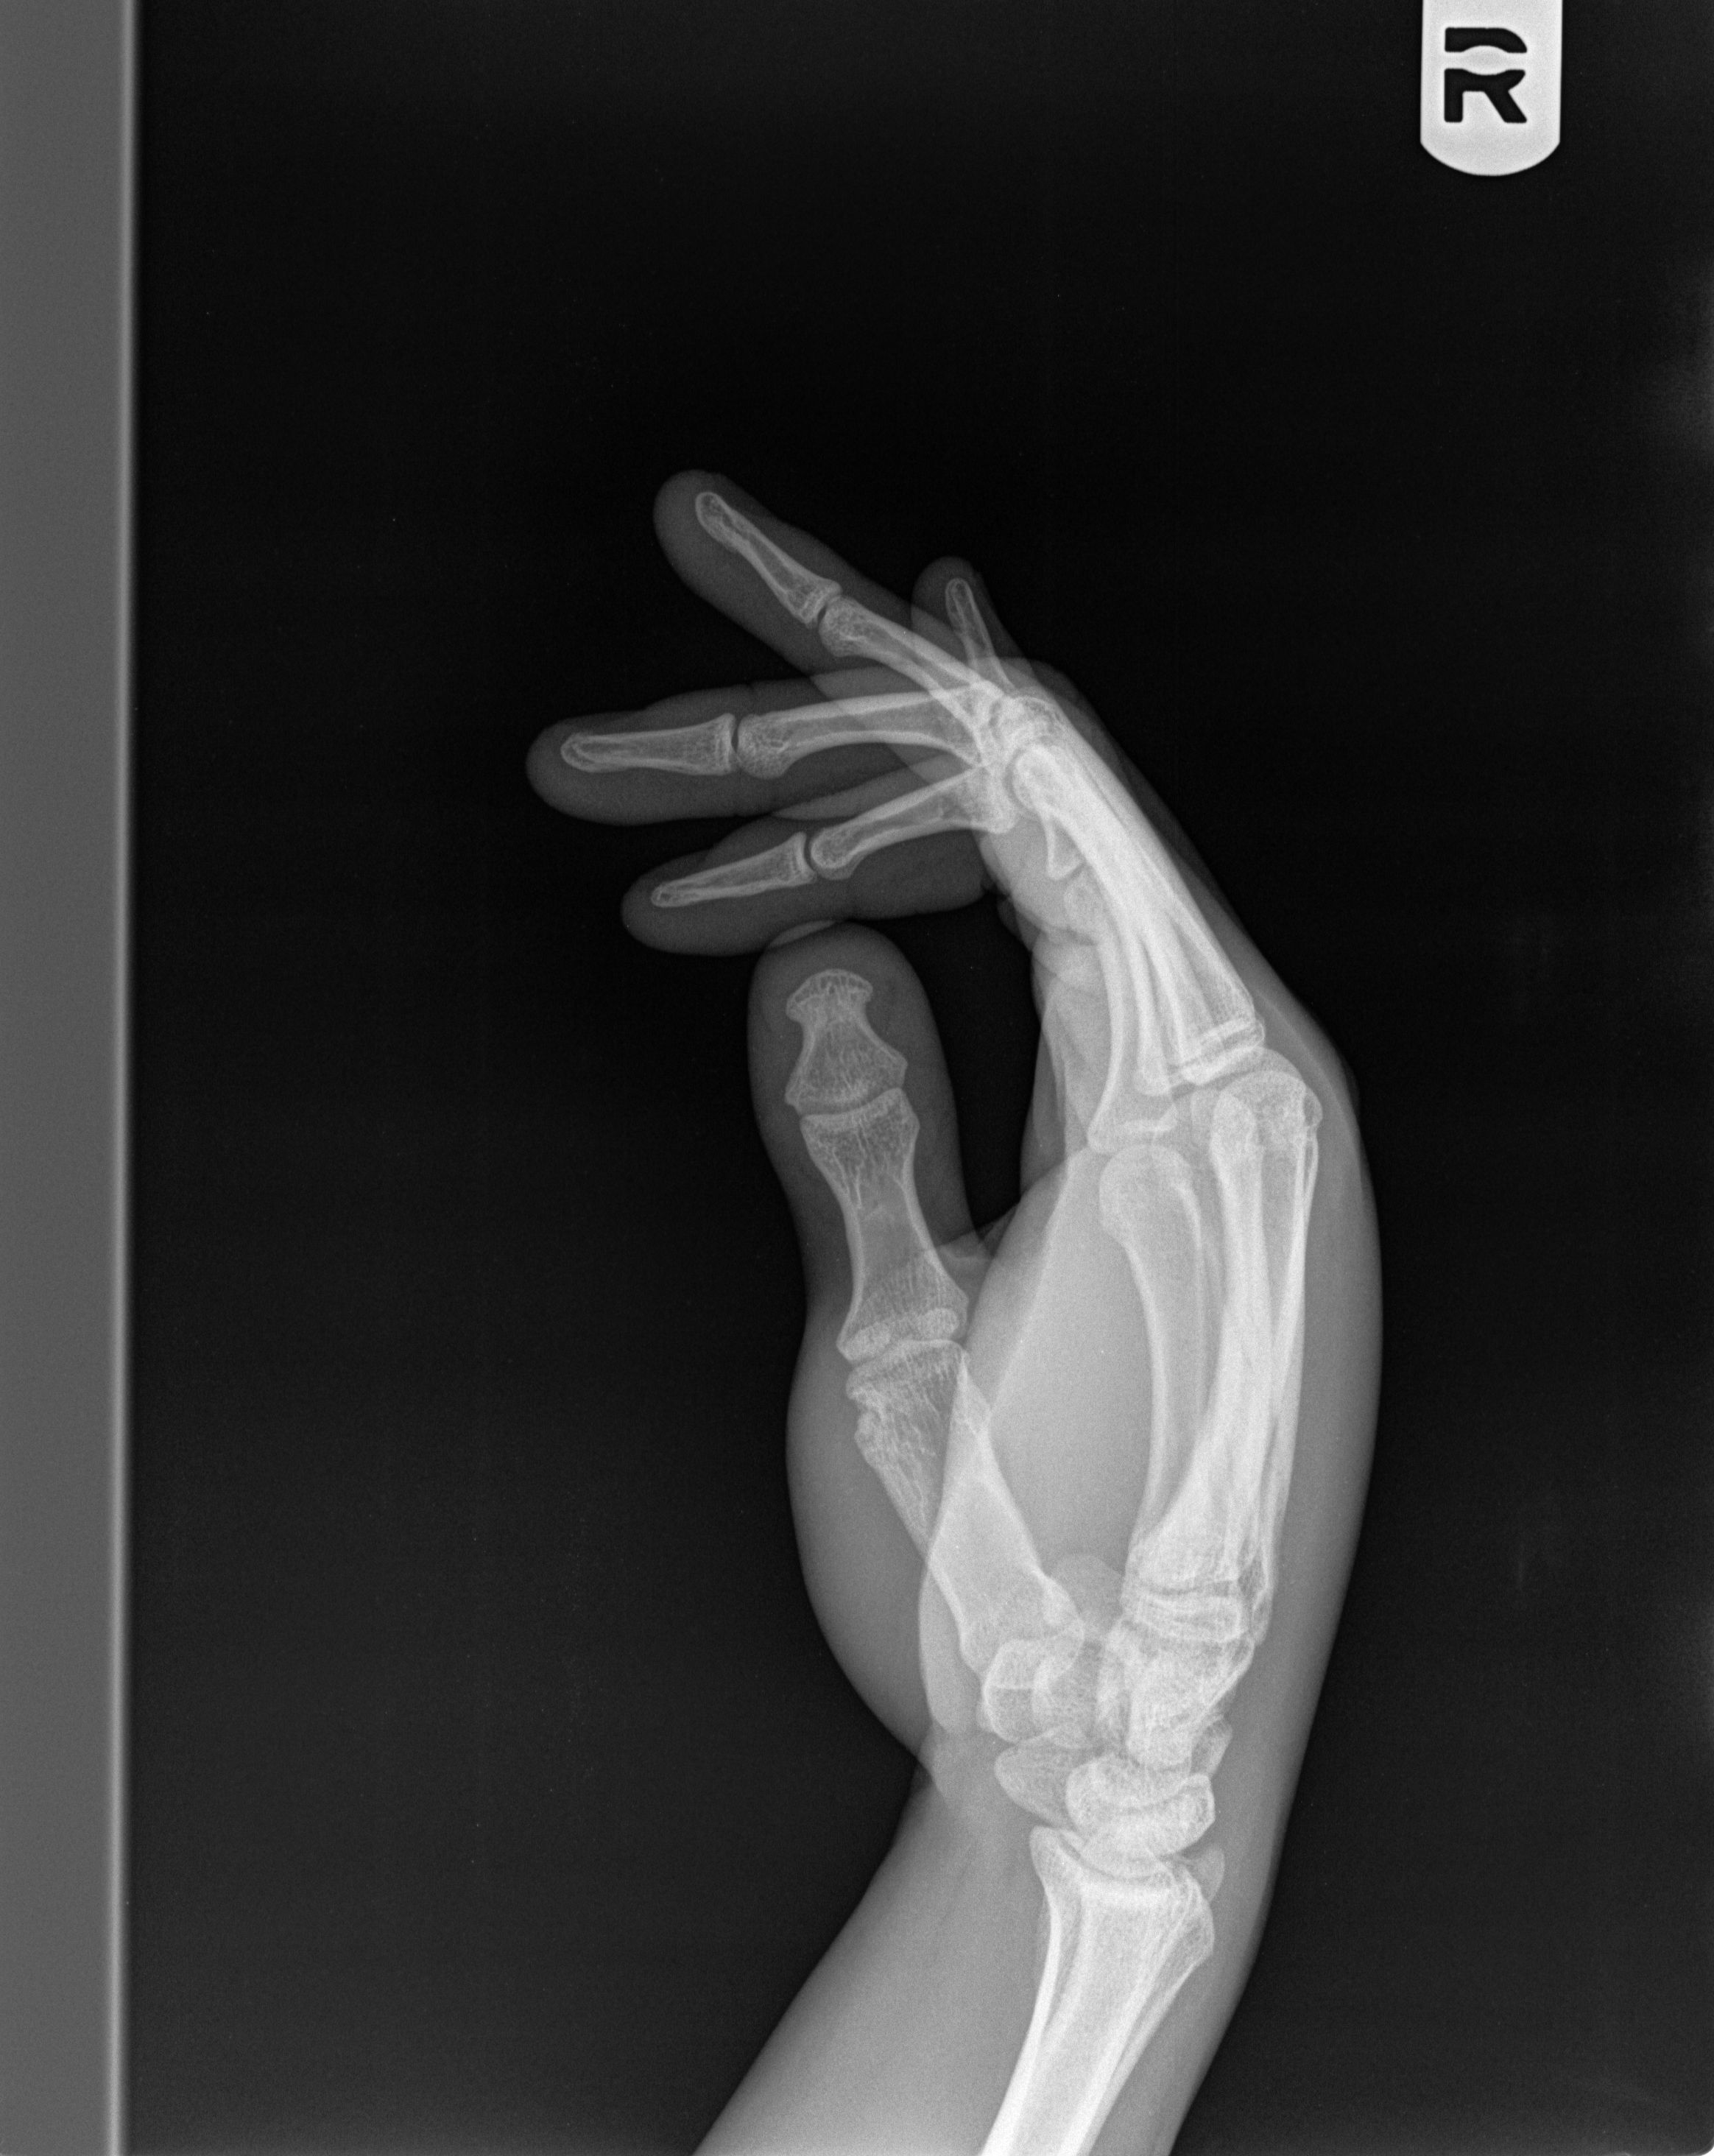

From www.jucm.com

Xray of man with a crush injury to hand Journal of Urgent Care Medicine Crush Injury With This type of injury most often happens when part of the body is squeezed. A crush injury occurs when force or pressure is put on a body part. Crush injury occurs with direct physical trauma to the body from an external force [ 3, 6, 11, 12 ]. Crush syndrome is the severe systemic. Crush syndrome (also traumatic rhabdomyolysis or. Crush Injury With.